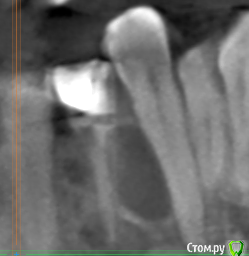

technodriver Опубликовано 18 марта, 2018 Автор Поделиться Опубликовано 18 марта, 2018 После операции прошло почти 3 недели. Швы сняты. Ощущение припухлости сохраняется. В области удаленного зуба имеется пара мест из которых вылезает по 2-3 белых крупинки в день... Ссылка на комментарий

red_butler Опубликовано 18 марта, 2018 Поделиться Опубликовано 18 марта, 2018 После операции прошло почти 3 недели. Швы сняты. Ощущение припухлости сохраняется. В области удаленного зуба имеется пара мест из которых вылезает по 2-3 белых крупинки в день...на снимке ничего критичного, для подстраховки покажитесь своему врачу 1 Ссылка на комментарий